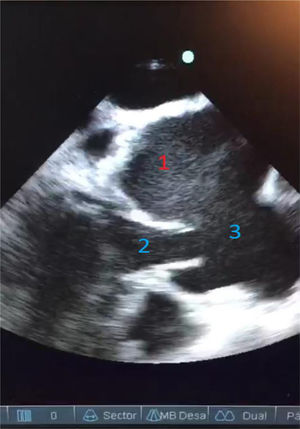

En un control de ecocardiografía, se observa válvula aórtica trivalva, insuficiencia leve y dilatación aneurismática del seno de Valsalva izquierdo. Buena función ventricular. Sin dilatación ventricular (fig. 2).

En la reunión de heart team, se plantearon varias alternativas dentro de las cuales estaba la endovascular o la quirúrgica. Había varios aspectos a tener en cuenta para la resolución del aneurisma. Uno de ellos, era la coronaria izquierda naciendo del fondo de este, ello llevaba a un gran problema endovascular, dado que no se podía excluir ese aneurisma sin afectarla. El otro componente en juego era la válvula aórtica que se encontraba solo con insuficiencia leve y en buenas condiciones, también generaba dudas sobre la resolución endovascular, si podría llegar a afectarla. Por todo lo mencionado, considerando la posibilidad de conservar la válvula y el reimplante de la coronaria izquierda, se decidió optar por la conducta quirúrgica, asumiendo el riesgo que acarrea una reoperación, dado que era la tercera cirugía cardiaca y, además, con la posibilidad de afectación de la válvula, lo cual llevaría al reemplazo. En el intraopertorio, realizamos un ecocardiograma donde se evidencia gran dilatación asociada al hematoma dentro de aneurisma (fig. 5).